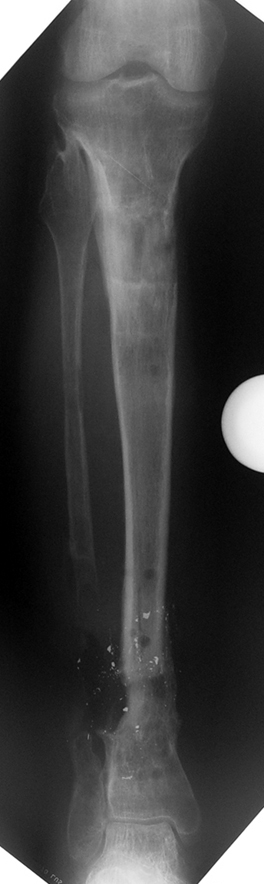

The bifocal compression technique described by Ilizarov, which consists of acute shortening and gradual distraction, allows acute shortening of 4-5 centimeters in tibial defects; defects exceeding this amount can be further shortened gradually by 3 millimeters per day. The same principle is also applicable to the femur, allowing an acute shortening of 8 centimeters. This method facilitates reconstruction of bony continuity and primary or delayed primary closure of soft tissue defects, which would would avoid the requirement for free flaps. A second corticotomy in the metaphyseal region may be used to restore the original length of the shortened bone and to increase it’s vascularity. Intramedullary osteosynthesis of intra-/periarticular fractures is a borderline indication. Open reduction and internal fixation of these fractures hazards the blood supply to (small) bone fragments by extensive dissection, and nonunion or infection is (iatrogenically) invited. In contrary, percutaneous or indirect reduction by limited dissection, small wire and percutaneous cannulated screw osteosynthesis, augmented by external fixation, provides a stable construction to allow early mobilization, range of motion exercises and sometimes partial weight bearing.

My preference in these cases is to use circular external fixators, which are modular, permit fixation of small reduction wires to the frame, and enable postoperative angular adjustments. Recently, combined techniques using external fixators and intramedullary rods have been introduced. The advantage of this method is to decrease the external fixation time by about 50% and to enhance the patient’s comfort.

Case 4